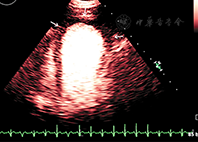

距离探头最近区域和聚焦区域的造影剂微泡破裂严重。如果是实时观察左室影像,由于气泡的破坏可观察到无造影剂增强或心尖区涡流。近场涡流成因是多因素的,主要成因是MI设置过高或注射造影剂剂量不足。通过及时注入新制备的造影剂进入心室腔补充或代替被破坏掉的造影剂的方法可以使涡流伪像消失;如果血流缓慢,新注入的造影剂未能及时充分替代被破坏的造影剂,则在流速最低的区域或高MI时,还会有涡流伪像。生理原因引起的心尖部血流速度超低(严重左心功能不全或心尖部大的室壁瘤)也是涡流伪像的常见原因(图1)。